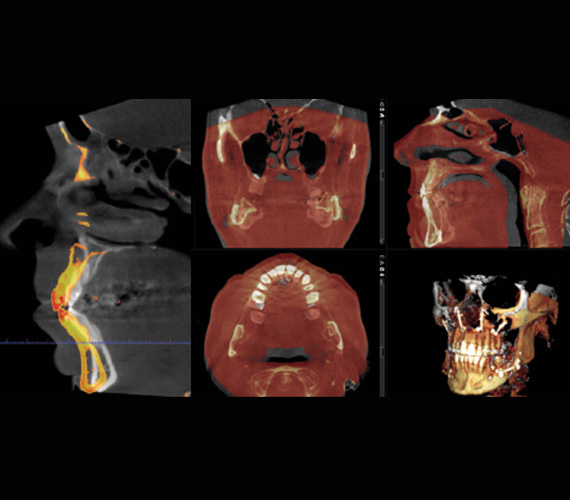

The Romexis software’s 3D rendering view provides an immediate overview of a patient’s anatomy and serves as an excellent tool for patient education. It allows you to instantly view images from different projections or converted into panoramic images and cross-sectional slices. The software’s measuring and annotation tools – such as nerve canal tracing – further support safe and accurate treatment planning.

CBCT images are ideal for orthodontic diagnoses and the Romexis software makes it easy to analyse skeletal symmetry, detect unerupted and supernumerary tooth positions, as well as identify root resorption and orientation accurately. The software can also create cephalometric images and panoramic views from CBCT images to be used for cephalometric analyses.